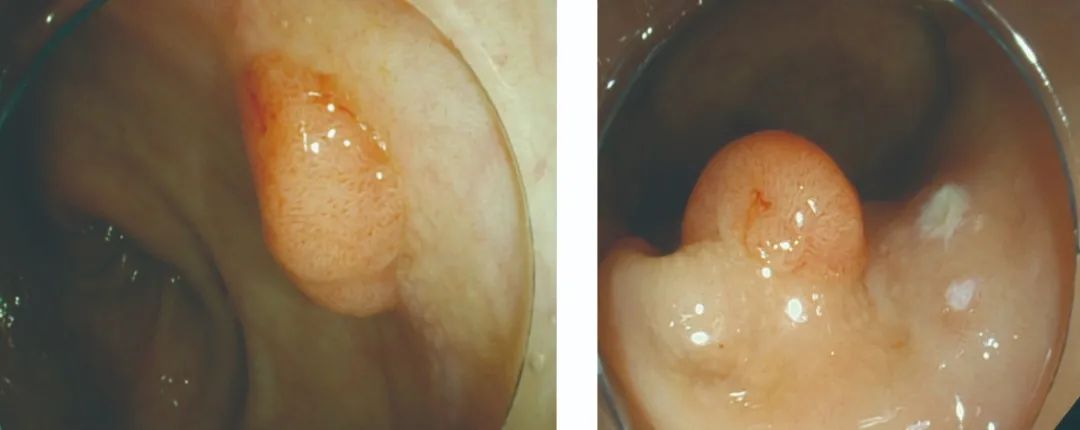

肠镜检查:直肠可见1CM大小广基扁平肿物

病理诊断:直肠绒毛状腺瘤 中度异形可见核分裂像

▲ 镜下高清画质,放大病灶